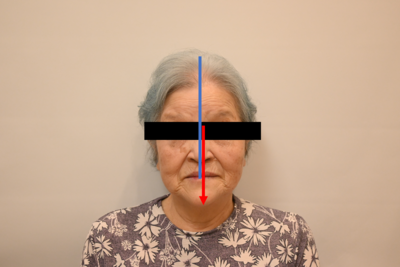

お顔の写真:正面

お顔の写真を見てみましょう。正面から見るとそんなに顎が曲がっているようには見えません。

顎は、お鼻のラインに対して少し向かって左寄りに見えます。

下顎は、向かって左側に若干ズレているように見えます。

上あごと下あごの正中が合っていません(写真:赤線と青線)。ということは噛み合わせも合っていないということになります。患者さまの顎がズレているのか、入れ歯の排列した歯がズレているのか、またはその両方なのかを考えながら作る必要があります。